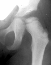

A ten year old female presented with a left hip dislocation. She was born by Cesarean-section because of slow progression of labor. The child was not breech and was noted to have a dislocatable hip at birth. There was a negative family history of DDH. An X-ray prior to application of the brace showed the dislocation of the hip. The patient was first seen at AIDI on 9th day. Abduction of the right hip was 80 degrees but left was only 60 degrees. There was a positive Galeazzi sign with the left hip being shorter than the right. X-rays showed a left hip dislocation and right hip subluxation . A Pavlik harness was applied. After two months, the right hip improved but the left hip was still dislocatable. For this, home traction was started. Even after 2 months, the left hip did not reduce. Therefore, an arthrogram, adductor tenotomy and closed reduction was done at 4 months of age. Single hip spica was applied with the hip in 40 abduction and 100 flexion. Eight weeks later an arthrogram was performed and the cast was reapplied with the hip in 35 degrees abduction and 100 degrees flexion.

Four months later, the spica cast was removed and an Atlanta brace was applied. X-rays showed avascular necrosis at ten months of age . At two years of age, the ossification of the left nucleus was still delayed. The leg lengths were equal and the range of motion of the hip was full.

The progression of the hip is documented by x-rays taken at 1 year of age, 2 years of age, 3 years of

age, 5 years of age, 7 years of age, then at ten years of age, early closure of the lateral portion of proximal growth plate observed. Coxa valga was also observed.